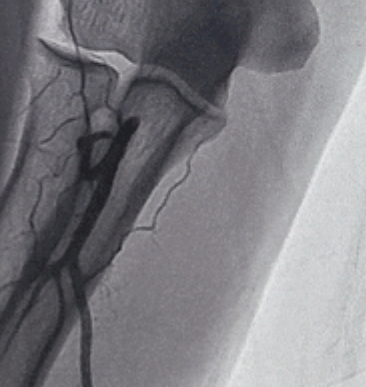

图1 造影提示桡动脉弯曲成环

图2 以PTCA导丝通过弯曲